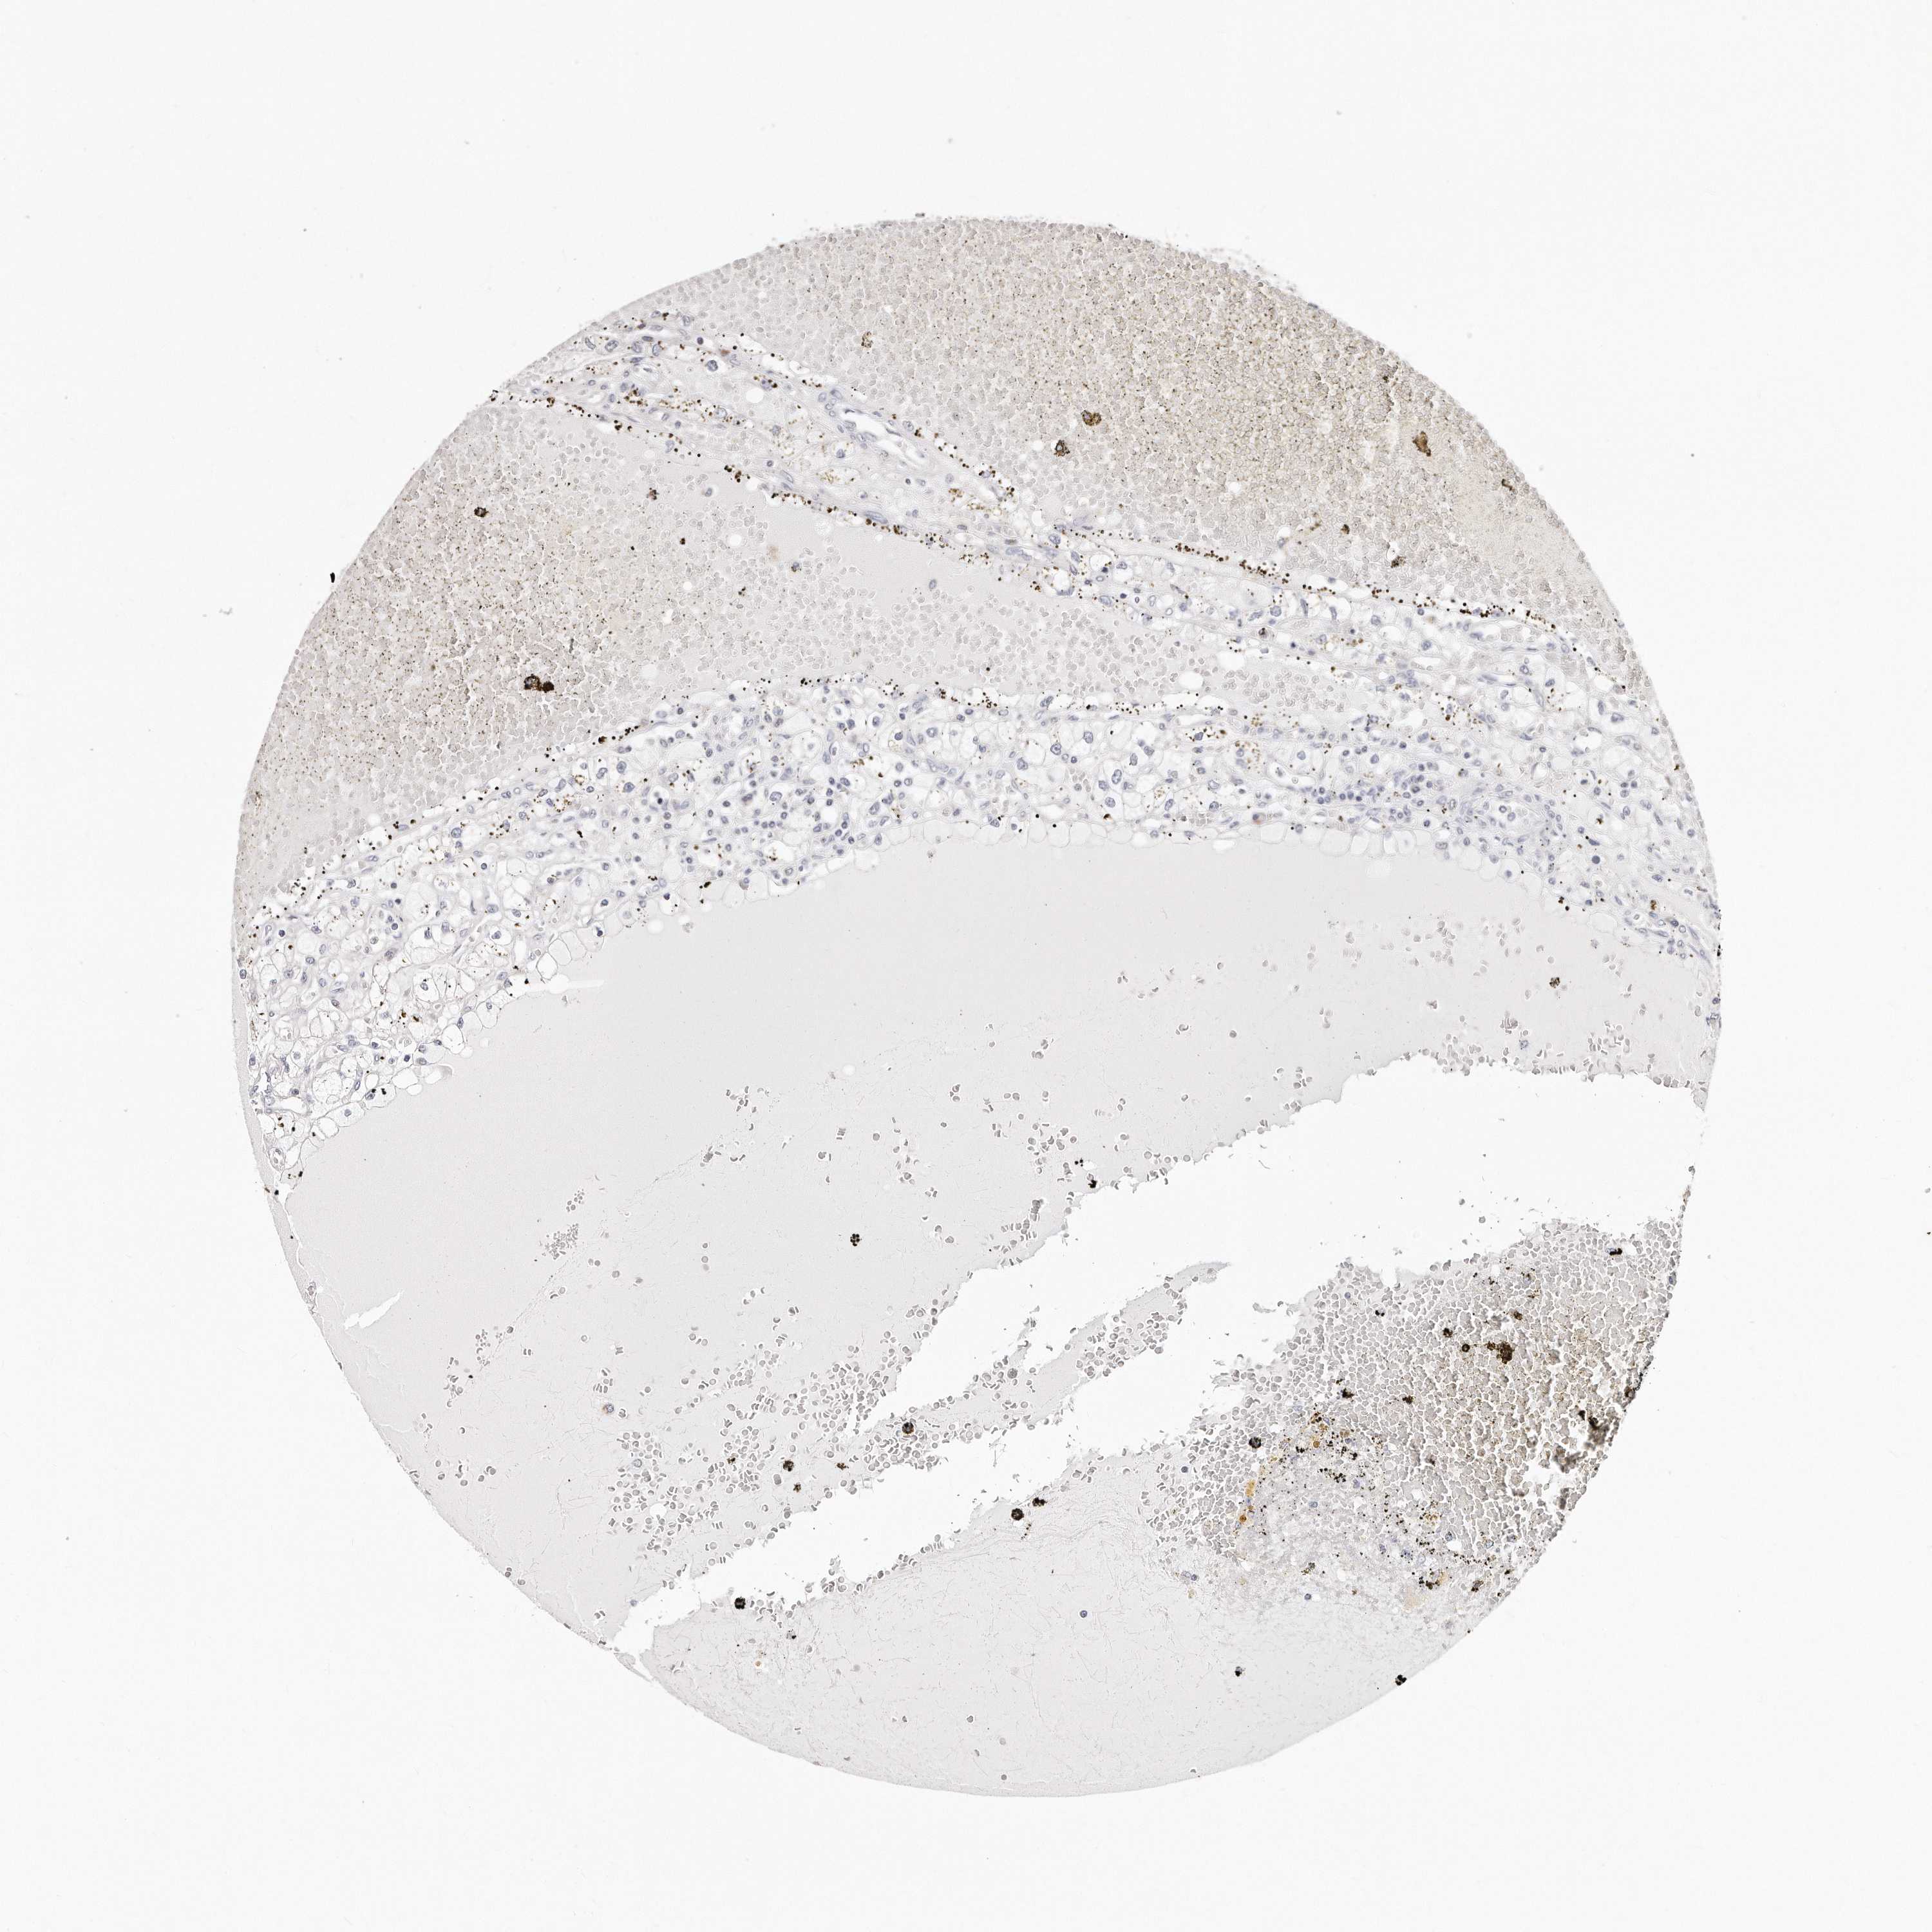

KIDNEY RENAL CLEAR CELL CARCINOMA (VALIDATION) - Interactive survival scatter ploti

The Survival Scatter plot shows the clinical status (i.e. dead or alive) for all individuals in the patient cohort, based on the same data that underlies the corresponding Kaplan-Meier plots. Patients that are alive at last time for follow-up are shown in blue and patients who have died during the study are shown in red.

The x-axis shows the expression levels (FPKM) of the investigated gene in the tumor tissue at the time of diagnosis. The y-axis shows the follow-up time after diagnosis (years). Both axes are complimented with kernel density curves demonstrating the data density over the axes. The top density plot shows the expression levels (FPKM) distribution among dead (red) and alive patients (blue). The right density plot shows the data density of the survived years of dead patients with high and low expression levels respectively, stratified using the cutoff indicated by the vertical dashed line through the Survival Scatter plot. This cutoff is automatically defined based on the FPKM cutoff that minimizes the p-score. The cutoff can be changed by dragging the vertical line or by entering a cutoff value in the square labeled "Current cut-off".

Under the Survival Scatter plot the p-score landscape (black curve; left axis) is shown together with dead median separation (red curve; right axis). Dead median separation is the difference in median mRNA expression between patients who have died with high and low expression, respectively. It is calculated as follows: median FPKM expression of dead patients with high expression - median FPKM expression of dead patients with low expression. This is intended to aid the user in visually exploring custom cutoffs and the associated p-scores and dead median separation.

Individual patient data is displayed and can be filtered by clicking on one or more of the category buttons on the top of the page. Categories describing expression level and patient information include: high, low, alive, dead, female, male and tumor stages. The scale of the x-axis can be toggled between linear and log-scale by clicking on the "x log" button. Mouse-over function shows TCGA ID, patient information and mRNA expression (FPKM) for each patient.

& Survival analysisi

Kaplan-Meier plots summarize results from analysis of correlation between mRNA expression level and patient survival. Patients were divided based on level of expression into one of the two groups "low" (under cut off) or "high" (over cut off). X-axis shows time for survival (years) and y-axis shows the probability of survival, where 1.0 corresponds to 100 percent.

RTKN is not prognostic in Kidney Renal Clear Cell Carcinoma (validation)

Best expression cut offi

Based on the FPKM value of each gene, patients were classified into two groups and association between prognosis (survival) and gene expression (FPKM) was examined. The best expression cut-off refers the FPKM value that yields maximal difference with regard to survival between the two groups at the lowest log-rank P-value. Best expression cut-off was selected based on survival analysis .

When clicking on this number, the vertical dashed line indicating cut-off, the interactive survival plot, and the Kaplan-Meier curve will be adjusted to show results based on the best expression cut-off.

: 38.17

TCGA RNA samplesi

RNA-seq data is reported as average FPKM (number Fragments Per Kilobase of exon per Million reads), generated by the The Cancer Genome Atlas (TCGA) .

Normal distribution across the dataset is visualized with box plots, shown as median and 25th and 75th percentiles. Points are displayed as outliers if they are above or below 1.5 times the interquartile range. FPKM values of the individual samples are presented next to the box plot.

Average pTPM 57.0

Number of samples 100